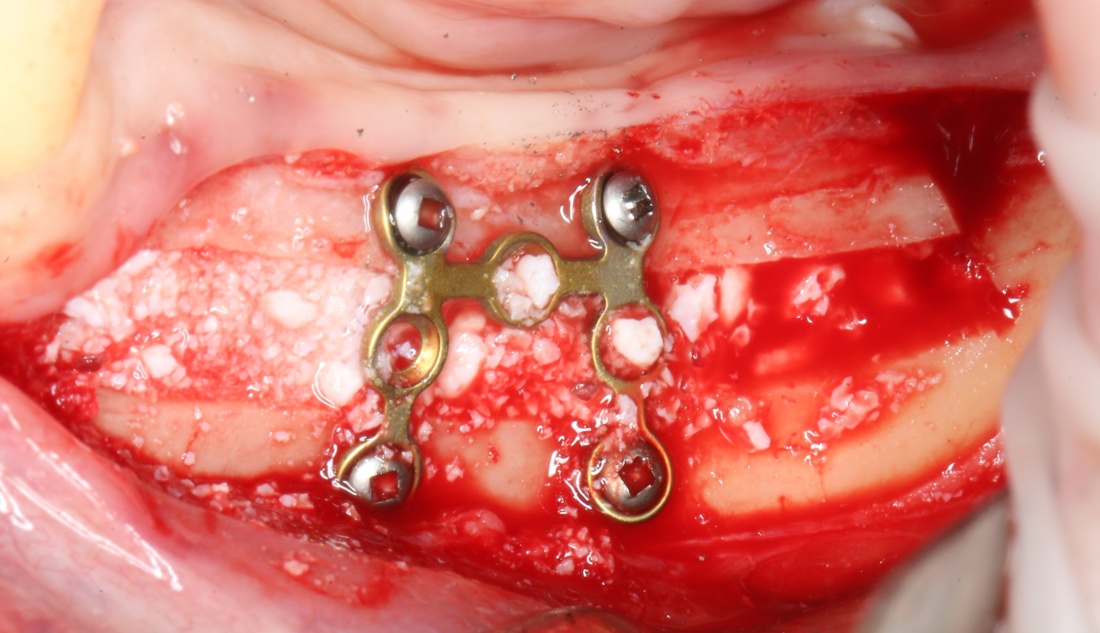

В какой момент это делать? Наверное, если Вы используете графт в виде твердого блока, то, мне кажется. разумнее сначала уложить графт, затем проводить фиксацию перемещенного костного фрагмента винтами или минипластинами:

И наоборот, если вы применяете графт в виде гранул (типа, Bio-Oss L), то, для начала, нужно зафиксировать костный фрагмент, затем укладывать графт.

Я не рекомендую «прессовать» графт, как это делают некоторые из докторов. Во-первых, имеет значение расстояние между гранулами, ведь, по идее, туда должна прорасти собственная костная ткань. Во-вторых, частицы графта ломаются, и он превращается в порошок. В третьих, активным прессованием можно выдавить графт, куда угодно. Например, в челюстно-язычный желобок. Приятного в этом, согласитесь, мало.